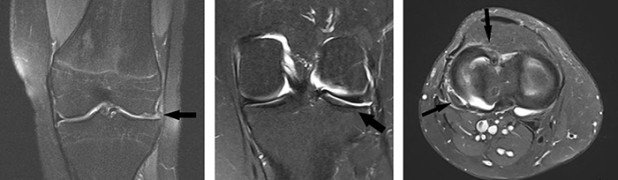

Die konventionelle radiologische Untersuchung zeigte eine gerade Beinachse mit ansonsten unauffälligen Befunden der Knochen. Im durchgeführten MRT zeigte sich eine wahrscheinlich ältere Korbhenkelverletzung des Aussenmeniskus mit praktisch vollständigem Meniskusverlust im Vorderhorn und Corpus-Bereich. Zudem fand sich eine beginnende Knorpelausdünnung im lateralen Kompartiment ohne höhergradige Schäden als Zeichen eines schon länger bestehenden funktionellen Verlusts des Meniskus.

Mitte und rechts: Nach der Transplantation (Pfeil zeigt auf Implantat)